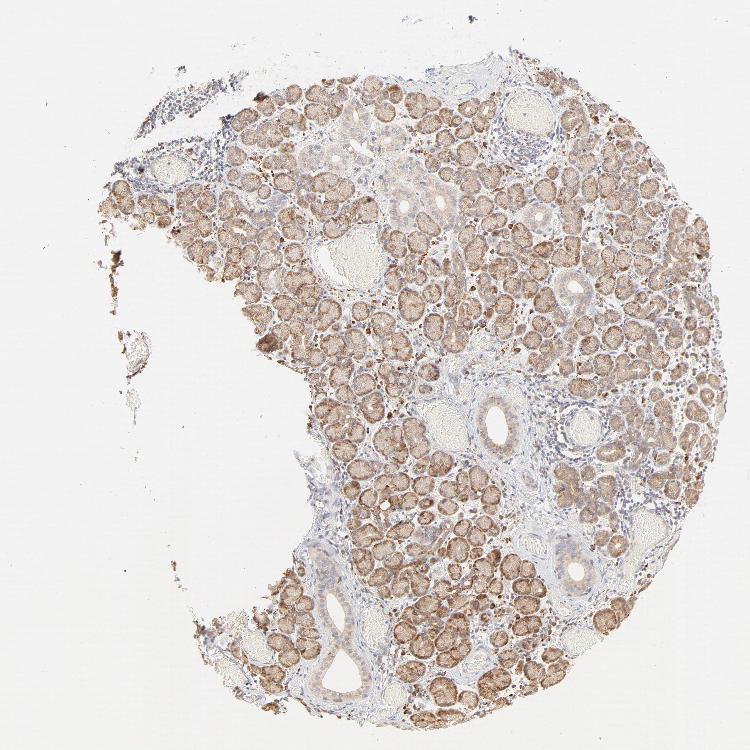

SALIVARY GLAND - Antibody stainingi

Antibody staining in the annotated cell types in the current human tissue is reported as not detected, low, medium, or high, based on conventional immunohistochemistry profiling in selected tissues. This score is based on the combination of the staining intensity and fraction of stained cells.

Each image is clickable and will lead to virtual microscopy that enables deeper exploration of all samples and also displays staining intensity scores, fraction scores and subcellular localization as well as patient and tissue information for each sample.

Antibody HPA003584

Glandular cells Medium